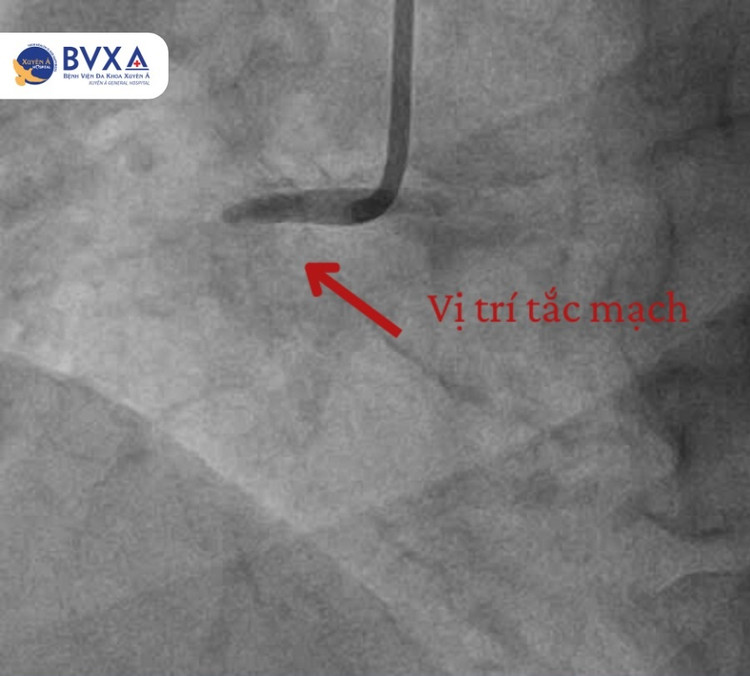

| Hình ảnh vị trí đoạn mạch bị tắc - Hình ảnh sau khi thông - Ảnh BVCC |

Dựa trên kết quả chụp mạch vành, các bác sĩ phát hiện người bệnh bị tắc hoàn toàn đoạn gần của động mạch vành phải. Trước tình hình này, ê-kíp bác sĩ khoa Can thiệp Tim mạch đã tiến hành can thiệp nong và đặt stent tại vị trí tắc mạch.

Chỉ sau 45 phút, một stent đã được đặt thành công giúp dòng máu tái thông hoàn toàn. Sau vài ngày theo dõi, điều trị tại khoa Nội tim mạch, tình trạng người bệnh dần ổn định, phục hồi rất tốt, được xuất viện và tái khám định kỳ theo hướng dẫn của bác sĩ.